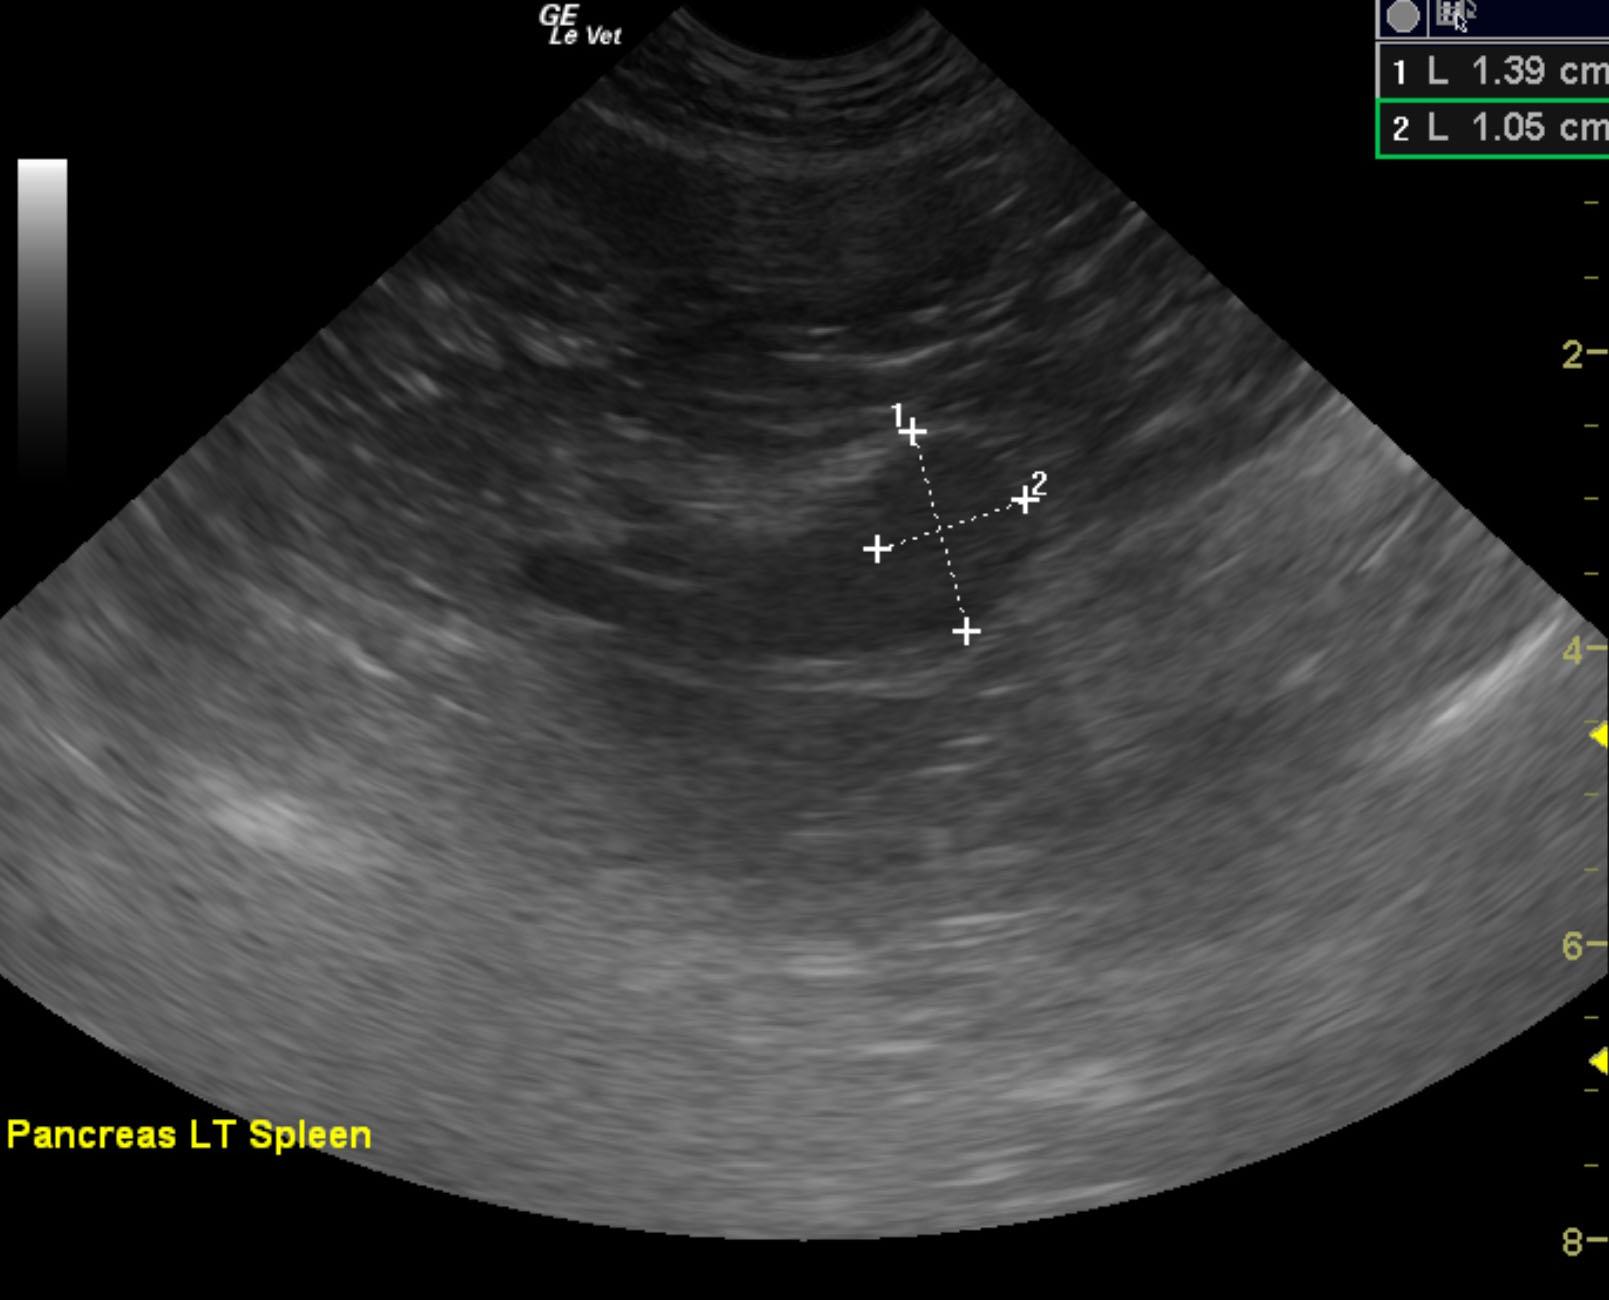

The left pancreatic limb revealed a 2 x 1.5 cm, hypoechoic nodule. The nodule was strongly vascular.

This is consistent with pancreatic nodule at the caudal pole of the left pancreatic limb or potentially a regional lymph node. This is strongly suspicious for metastatic or localized insulinoma. This lesion is adjacent to the mesenteric artery. Therefore, it very well may be a lymph node.